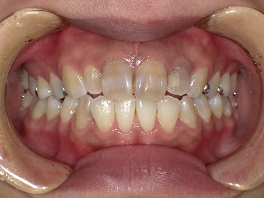

次の方は、歯を全く削らずにきれいにしてほしいということで、大阪から来られた患者さんの左上の前の歯4本を、グラディアで白くしてみました。

歯を全く削らず、表面をナノシールで処理して、グラディアで30分くらいの施術でした。

術前 ↓

術後

右側のすでに被せてある茶色く変色している歯は、大阪の家の近くの歯医者さんで、今回白くなった色に合わせて、被せなおしてもらうとのことです。